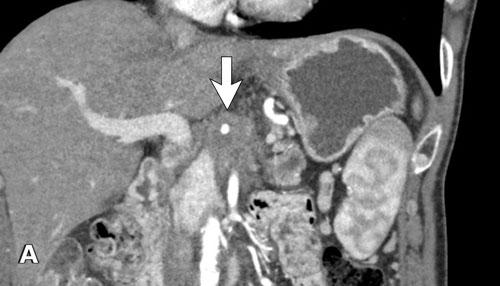

Tái tạo mặt phẳng coronal cho thấy một khối u lớn xuất phát từ cổ tụy với kiểu phát triển xâm lấn (hình A và B).

Có hiện tượng bao quanh động mạch thân tạng 360º (mũi tên trong A).

CT axial MIP tại mức động mạch thân tạng cho thấy hẹp động mạch gan chung bị bao quanh (mũi tên), rất nghi ngờ xâm lấn.